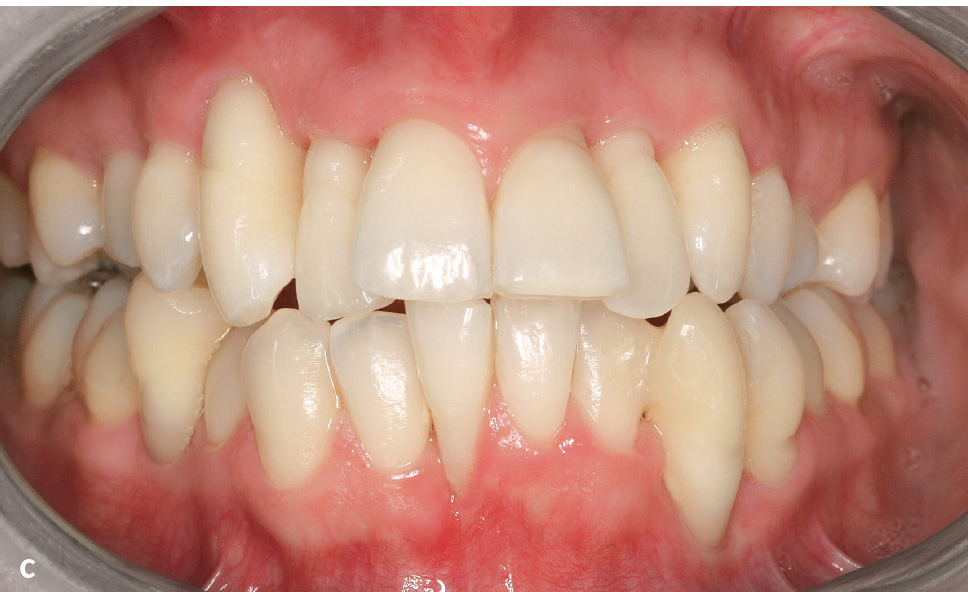

Abb. 1a bis d Parodontitis: a) Mann im Alter von 52 Jahren, Parodontitis, generalisiertes Stadium III, Grad C10: klinische Ansicht (Zahnfehlstellungen im Ober- und Unterkieferfrontzahnbereich, 31 Zahnstein); b) Röntgenstatus zu Abb. 1a: generalisierter überwiegend horizontaler Knochenabbau unterschiedlichen Ausmaßes (bis ins koronale Wurzeldrittel: 15–13, 23, 37–33, 43–47 [bis 33 % der Wurzellänge]; mittlere Wurzeldrittel: 17, 16, 12–22, 24–27, 32–42 [> 33 % der Wurzellänge]; auch am gleichen Zahn (z. B. 36); c) Frau im Alter von 24 Jahren: Parodontitis, generalisiert Stadium III, Grad C10; d) Panoramaschichtaufnahme zu Abb. 1c: Während sich an den Seitenzähnen des 2. Quadranten praktisch kein Knochenabbau findet, weisen andere Zähne Knochenabbau bis ins apikale Wurzeldrittel auf (z. B. 13, 33).